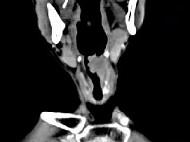

男,53岁,咽部不适半年余,近2个月感咽部疼痛,声嘶,CT如图所示,应诊断为 ( )

答案: D